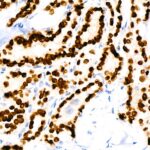

Images of TTF1 Rabbit mAb (A22248)

Immunohistochemistry analysis of paraffin-embedded Human lung adenocarcinoma using NKX2-1 Rabbit mAb (A22248) at dilution of 1:100 (40x lens).Perform high pressure antigen retrieval with 10 mM citrate buffer pH 6.0 before commencing with IHC staining protocol.